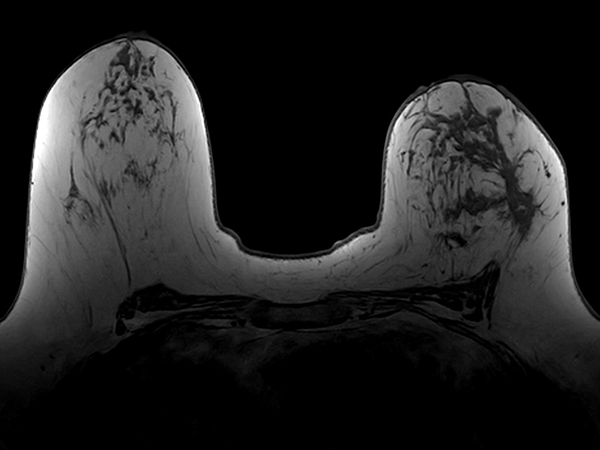

Axial T1w FFE